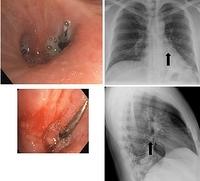

Metallic material

Metallic pins

Aspiration of a metallic pin